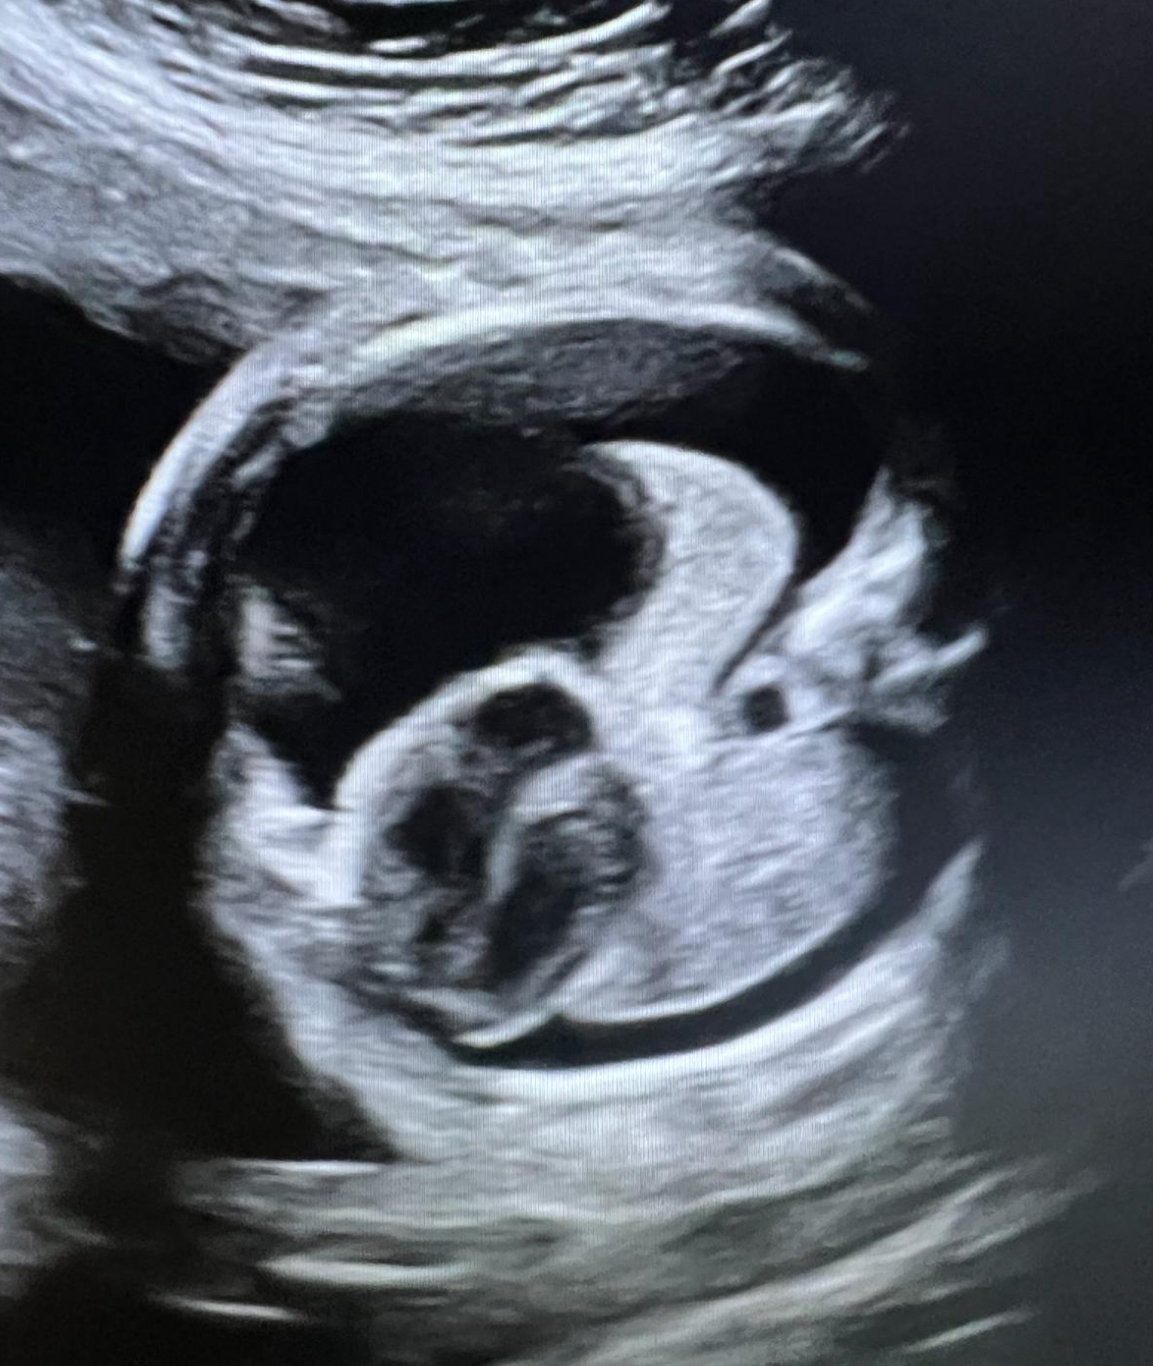

W ostatnich dniach w Klinice Położnictwa i Perinatologii Państwowego Instytutu Medycznego MSWiA w Warszawie wykonano kolejny zabieg z zakresu terapii płodu - po raz pierwszy w tej lokalizacji. U ciężarnej, będącej w 31 tygodniu ciąży, zdiagnozowano hydrothorax u płodu. Jest to nieprawidłowość, polegająca na obecności wolnego płynu w klatce piersiowej płodu, co uniemożliwia prawidłowy rozwój płuc i powoduje ich hypoplazję, jak również przemieszcza i uciska serce, prowadząc do niewydolności krążenia, która - w przypadku braku odpowiedniej terapii - może doprowadzić do śmierci płodu. Przyczyny takiego stanu mogą być natury genetycznej, infekcyjnej, endokrynologicznej, ale najczęściej pozostają nieznane - w takiej sytuacji rozpoznajemy postać idiopatyczną. Terapia hydrothorax polega na odbarczeniu płynu z klatki piersiowej płodu - można to uzyskać poprzez punkcję igłową, jednakże postępowanie takie jest mało efektywne, gdyż szybko dochodzi do nawrotu. Dlatego też metodą z wyboru jest założenie tzw. shuntu opłucnowo-owodniowego (cewnik typu double pig-tail), który umożliwia stały jednokierunkowy drenaż nadmiaru płynu.

Załączone zdjęcia pokazują zabieg (1), który wykonał zespół w składzie dr n. med. Michał Lipa i prof. dr hab. Mirosław Wielgoś oraz obrazy ultrasonograficzne, na których uwidoczniono sytuację wyjściową (2), założony shunt (3) i stan 4 dni po zabiegu (4). Doraźny efekt jest - jak widać na zdjęciach - bardzo dobry, w związku z czym Pacjentkę wypisano do domu. Z niecierpliwością oczekujemy na kontrolę, która odbędzie się w naszej Poradni Patologii Ciąży już za tydzień.